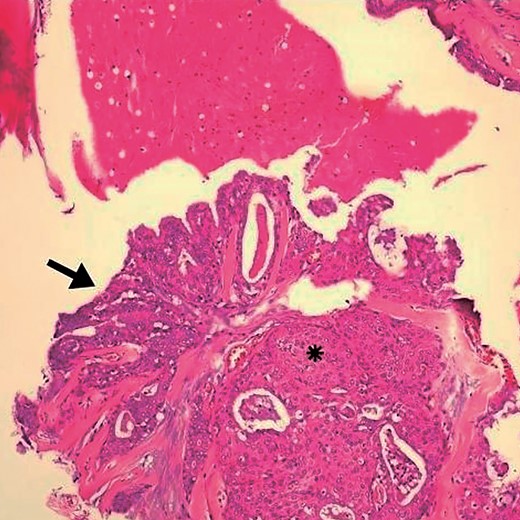

Arrows indicate the wall of a multilocular cyst without atypias. Black asterisk – non-invasive solid area with epidermoid alterations and low-grade atypias. White asterisk – invasive area with squamous and mucinous elements, suggesting the possibility of mucoepidermoid carcinoma. HE, ×4.